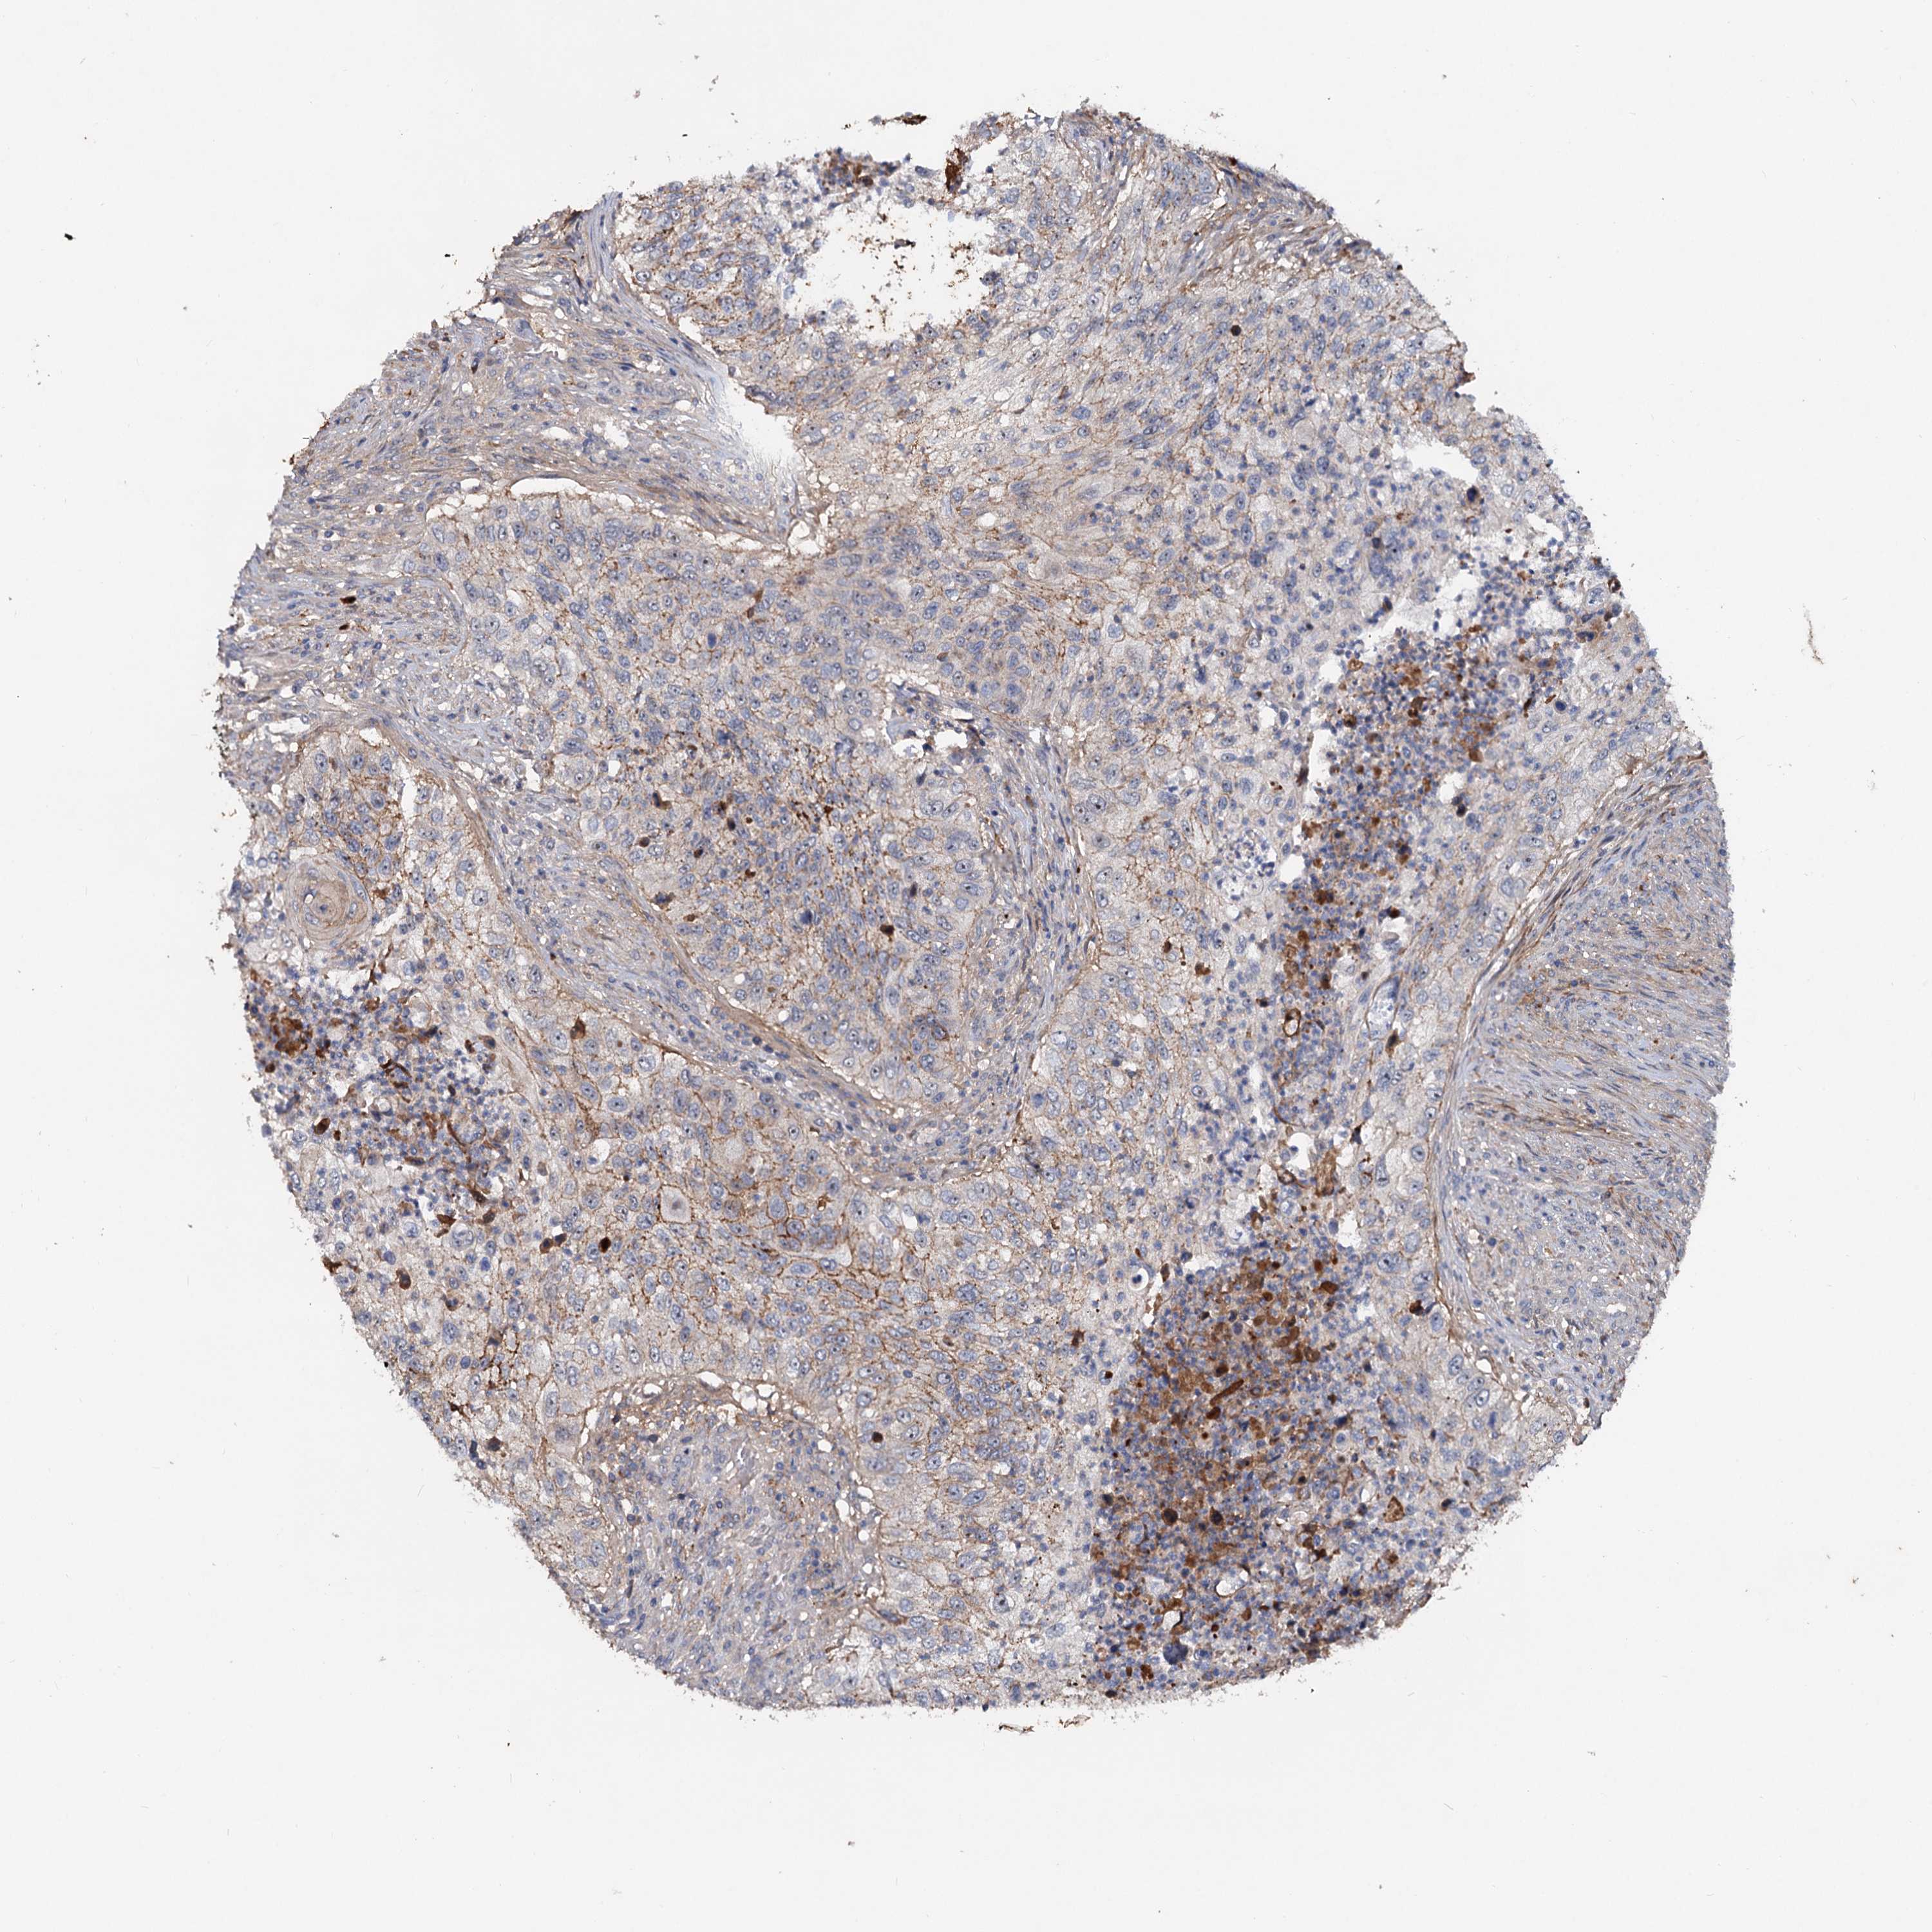

UROTHELIAL CANCER - Protein expressioni

A mouse-over function shows sample information and annotation data. Click on an image to view it in a full screen mode. Samples can be filtered based on level of antibody staining by selecting one or several of the following categories: high, medium, low and not detected. The assay and annotation is described here.

Note that samples used for immunohistochemistry by the Human Protein Atlas do not correspond to samples in the TCGA dataset.

Antibody stainingi

Antibody staining in the annotated cell types in the current human tissue is reported as not detected, low, medium, or high, based on conventional immunohistochemistry profiling in selected tissues. This score is based on the combination of the staining intensity and fraction of stained cells.

Each image is clickable and will lead to virtual microscopy that enables deeper exploration of all samples and also displays staining intensity scores, fraction scores and subcellular localization as well as patient and tissue information for each sample.

Antibody HPA035827

Staining

High

Medium

Low

Not detected

Intensity

Strong

Moderate

Weak

Negative

Quantity

>75%

75%-25%

<25%

None

Location

Nuclear

Cytoplasmic/membranous

Cytoplasmic/membranous,nuclear

Urothelial carcinoma, High grade

Urothelial carcinoma, Low grade